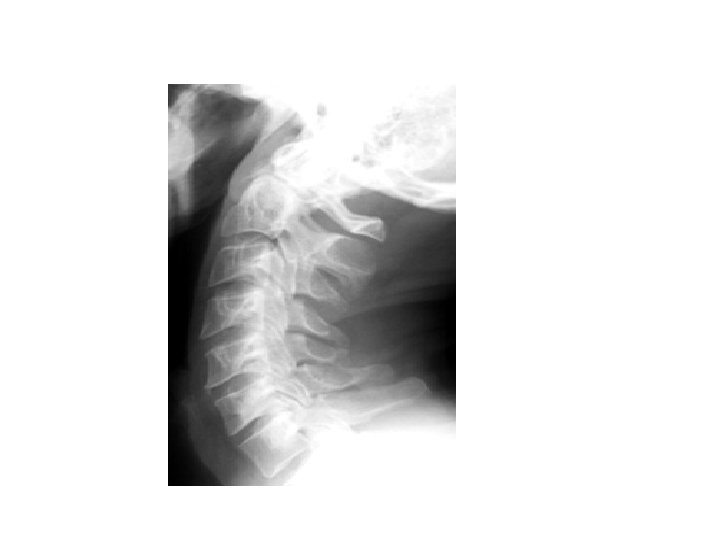

• • • Most important view Can see 80 -90% of injuries Interpretation: A - adequacy A - alignment B - bone C - cartilage D - disc S – soft tissue • • • A - Must have a view of C 7 – T 1 A - Use 3 lines 1. anterior vertebral line 2. posterior vertebral line 3. spino laminar line (base of spinous processes) 4 th line can be used ie. Tips of spinous processes •